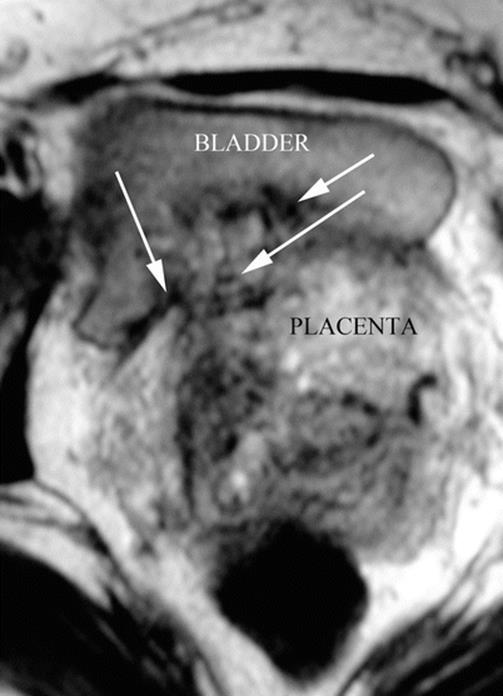

14.6 Placental MRI: Depth of Invasion

During a second stage, pMRI was requested to know the depth of placental invasion [10], especially to know whether the bladder is invaded. But bladder invasion is a vascular phenomenon, completely different from tissue invasion than neoplasia. In these cases, the placenta takes irrigation from the external layer of the bladder, but the state of uterine-bladder interface may be different according to thinning of myometrium, bladder wall, fibrous tissue between them or a combination of all these variables. For some authors, when the bladder is compromised, this is a formal indication to leave the placenta in situ, but this is not a really mandatory option. Placental MRI allows seeing this interface in great detail in axial T2 slices. When this series (axial T2) is performed perpendicularly to the posterior bladder wall, the anatomy of the placental-bladder interface is not distorted and shows a clear anatomy [13]. This interface can be distorted by peripheral circulation in a placental surface (engorged superficial vessels and lagoons) or by the presence of newly formed vessels between the placenta and the bladder. The presence of circular hypointensive signals (newly formed vessels) in the lower and posterior part of the bladder (cervicotrigonal area) is a reasonable sign of a very difficult dissection [13].

Axial MRI T1 image: axial slices made perpendicular to the posterior bladder wall are the most useful to see a vesical invasion. In this case, fibrous adherence between bladder and anterior myometrium is seen. White arrows: newly formed vessels. AIP type 2 (percreta)

Fig. 14.16